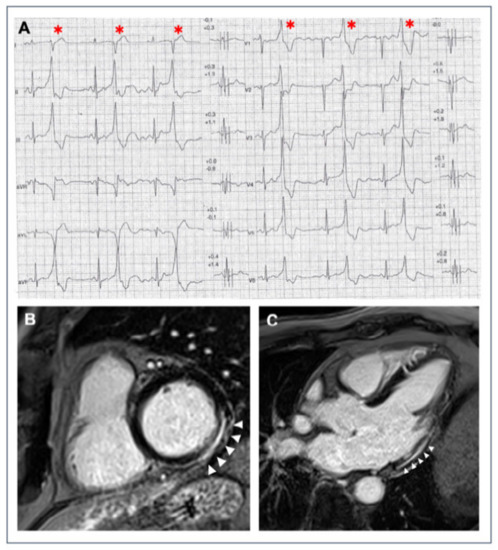

- Corrado, D.; Van Tintelen, P.J.; McKenna, W.J.; Hauer, R.N.W.; Anastastakis, A.; Asimaki, A.; Basso, C.; Bauce, B.; Brunckhorst, C.; Bucciarelli-Ducci, C.; et al. Arrhythmogenic right ventricular cardiomyopathy: Evaluation of the current diagnostic criteria and differential diagnosis. Eur. Heart J. 2020, 41, 1414–1429. [Google Scholar] [CrossRef]

- Cipriani, A.; Perazzolomarra, M.; Bariani, R.; Mattesi, G.; Vio, R.; Bettella, N.; de Lazzari, M.; Motta, R.; Bauce, B.; Zorzi, A.; et al. Differential diagnosis of arrhythmogenic cardiomyopathy: Phenocopies versus disease variants. Minerva Med. 2021, 112, 269–280. [Google Scholar] [CrossRef] [PubMed]

- Corrado, D.; Marra, M.P.; Zorzi, A.; Beffagna, G.; Cipriani, A.; De Lazzari, M.; Migliore, F.; Pilichou, K.; Rampazzo, A.; Rigato, I.; et al. Diagnosis of arrhythmogenic cardiomyopathy: The Padua criteria. Int. J. Cardiol. 2020, 319, 106–114. [Google Scholar] [CrossRef]